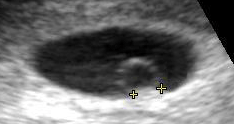

![]() Contents in the cavity of the uterus seen at approximately 5 weeks of gestational age by obstetric ultrasonography. | |

On obstetric ultrasound, the gestational sac is a dark ("anechoic") space surrounded by a white ("hyperechoic") rim.